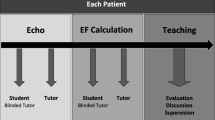

Participants were randomly assigned to four balanced groups (Fig. 1): first, to PLM or control and second, to receive test block A at pre-test and block B at post-test, or vice-versa.

All participants completed the assigned pre-test to establish a baseline rating of their ability to visually estimate LVEF. Participants in the PLM group then immediately underwent a single training session with the PLM. All participants subsequently completed their assigned post-test to measure their ability to visually estimate LVEF at the end of the first session. Controls thus visualized a total of 40 TEE exams (pre- and post-test), compared with 136 for the PLM group (20 pre-test, 96 PLM training, and 20 post-test). Participants were contacted via email six months after the first session and asked to complete a delayed post-test of the 20 TEE exams used in their baseline pre-test.